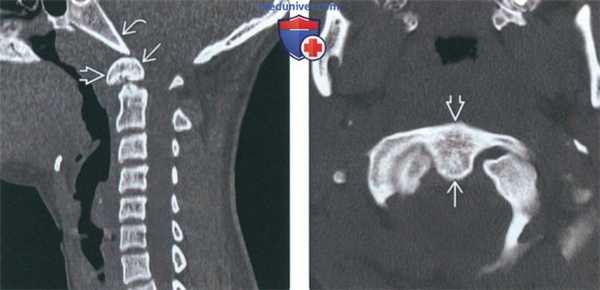

(Слева) На сагиттальной КТ шейного отдела позвоночника в костном окне определяется врожденное слияние передней дуги С1 и крупной зубовидной кости. Соотношение зубовидной кости со скатом не нарушено. Шейный отдел позвоночника ниже осевого позвонка в остальном не изменен, нарушения сегментации других позвонков не выявлены.

(Справа) На аксиальной КТ в костном окне определяется врожденное слияние орто-топической зубовидной кости с передней дугой С1 по средней линии. Задняя дуга С1 не имеет дефектов (на этом срезе не видна).